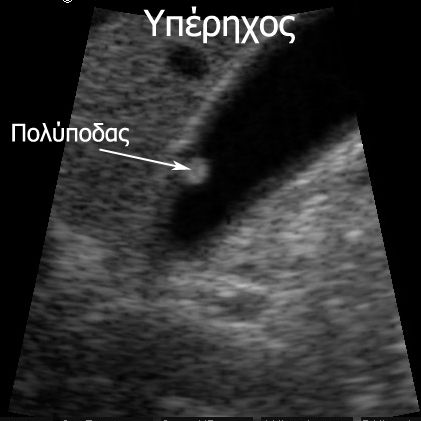

Στις περισσότερες περιπτώσεις όταν είναι <10mm συστήνεται τακτική παρακολούθηση με υπέρηχο. Αν μεγαλώσουν σε επόμενο έλεγχο τότε συστήνεται η αφαίρεση με λαπαροσκοπική χολοκυστεκτομή.

Οι πολύποδες που είναι μεγαλύτεροι από 10 χιλιοστά και κυρίως αυτοί που είναι σχεδόν 20χιλιοστά έχουν υψηλή πιθανότητα να μετατραπούν σε καρκίνο (εάν δεν είναι ήδη!) Αυτό σημαίνει ότι υπάρχει απόλυτη ένδειξη για την αφαίρεση τους με λαπαροσκοπική

χολοκυστεκτομή.

Να σημειωθεί και πάλι πάντως ότι μόνο το 5% παρουσιάζει κακοήθεια.

Αφαίρεση συστήνεται και στις περιπτώσεις που υπάρχει μόνο ένας πολύποδας ακόμα και είναι μικρότερος από 10 χιλιοστά, επίσης αν συνυπάρχουν πέτρες στη χολή ή εάν ο ασθενής έχει συνοδά νοσήματα όπως σακχαρώδη διαβήτη.